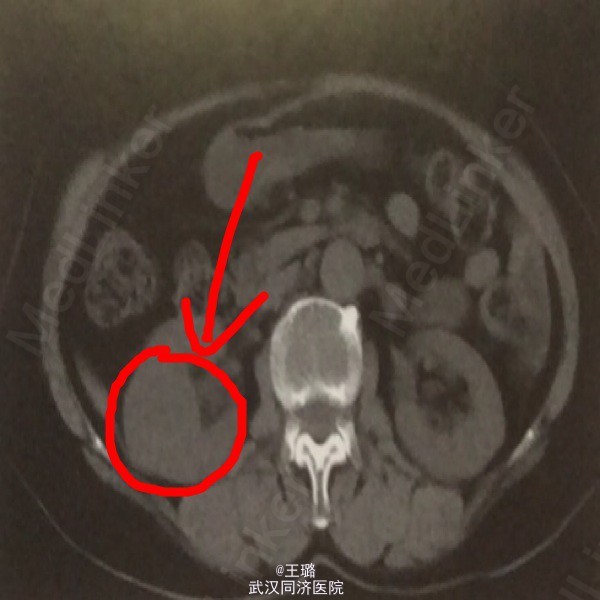

患者,女,65岁 因“右腰痛伴间断性肉眼血尿10余天”入院,患者10天前出现阵发性腰痛,可自行缓解,疼痛发作时伴有发热。晨起小便血色。

体检:面色贫血貌,肾区叩诊阳性,余为阴性。实验室检查:血常规:白细胞正常,红细胞降低,Hb:105;血生化:肌酸增高,白蛋白降低。血沉增快。电解质:钙离子升高。影像学检查:IVP示:右肾上盏稍有扩张,小盏杯口变圆钝。CT平扫示右肾中部类圆形低密度影,边界欠清。

诊断:右肾炎肌纤维母细胞瘤(术后病理) 治疗:腹腔镜下手术切除占位灶,术后给予肾炎常规激素治疗。